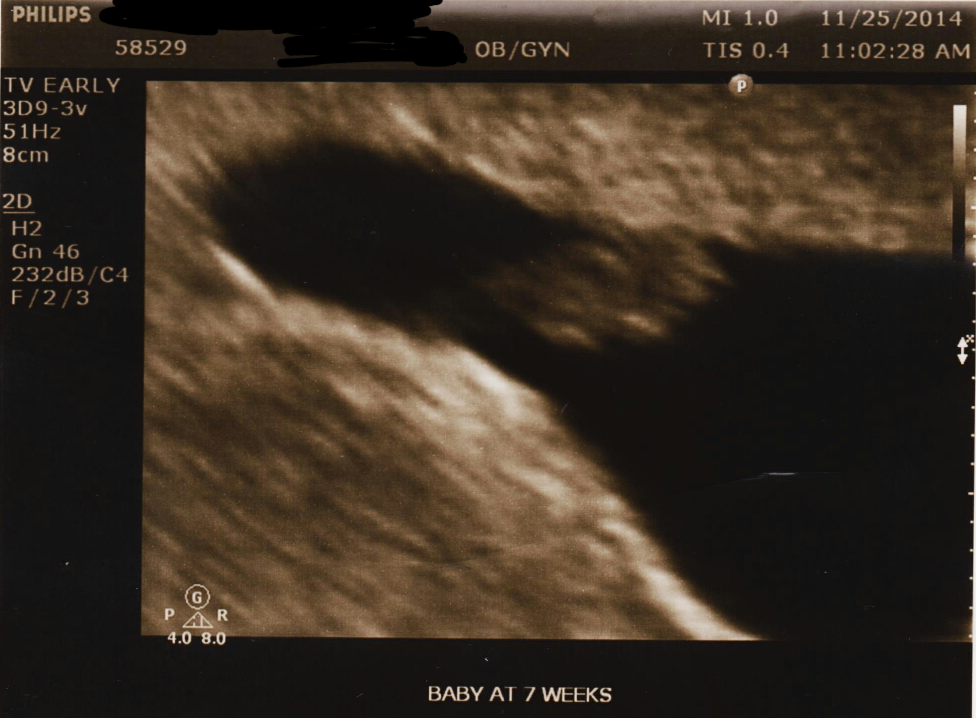

When I scheduled my first prenatal appointment, I was told that the office will not do an ultrasound until the doctor orders one for a later appointment. This was even confirmed with a follow up call just to check! So I was over the moon when I got there and the first thing they wanted to do was an ultrasound!

Since I didn't drink the water they normally would ask you to, the regular ultrasound scan wasn't showing a whole lot. I actually panicked a little bit until she suggested we try a transvaginal scan! I was so relieved when she said the heart beat looked strong! It measures out at 7weeks+2 days. This is our first and we tried for a year to get here, so needless to say we are extremely excited about this little blob!

• Thanks ladies! I feel like my u/s looks pretty different from everyone elses, I'm guessing because it was internal? Anyone else get one that looks like this?